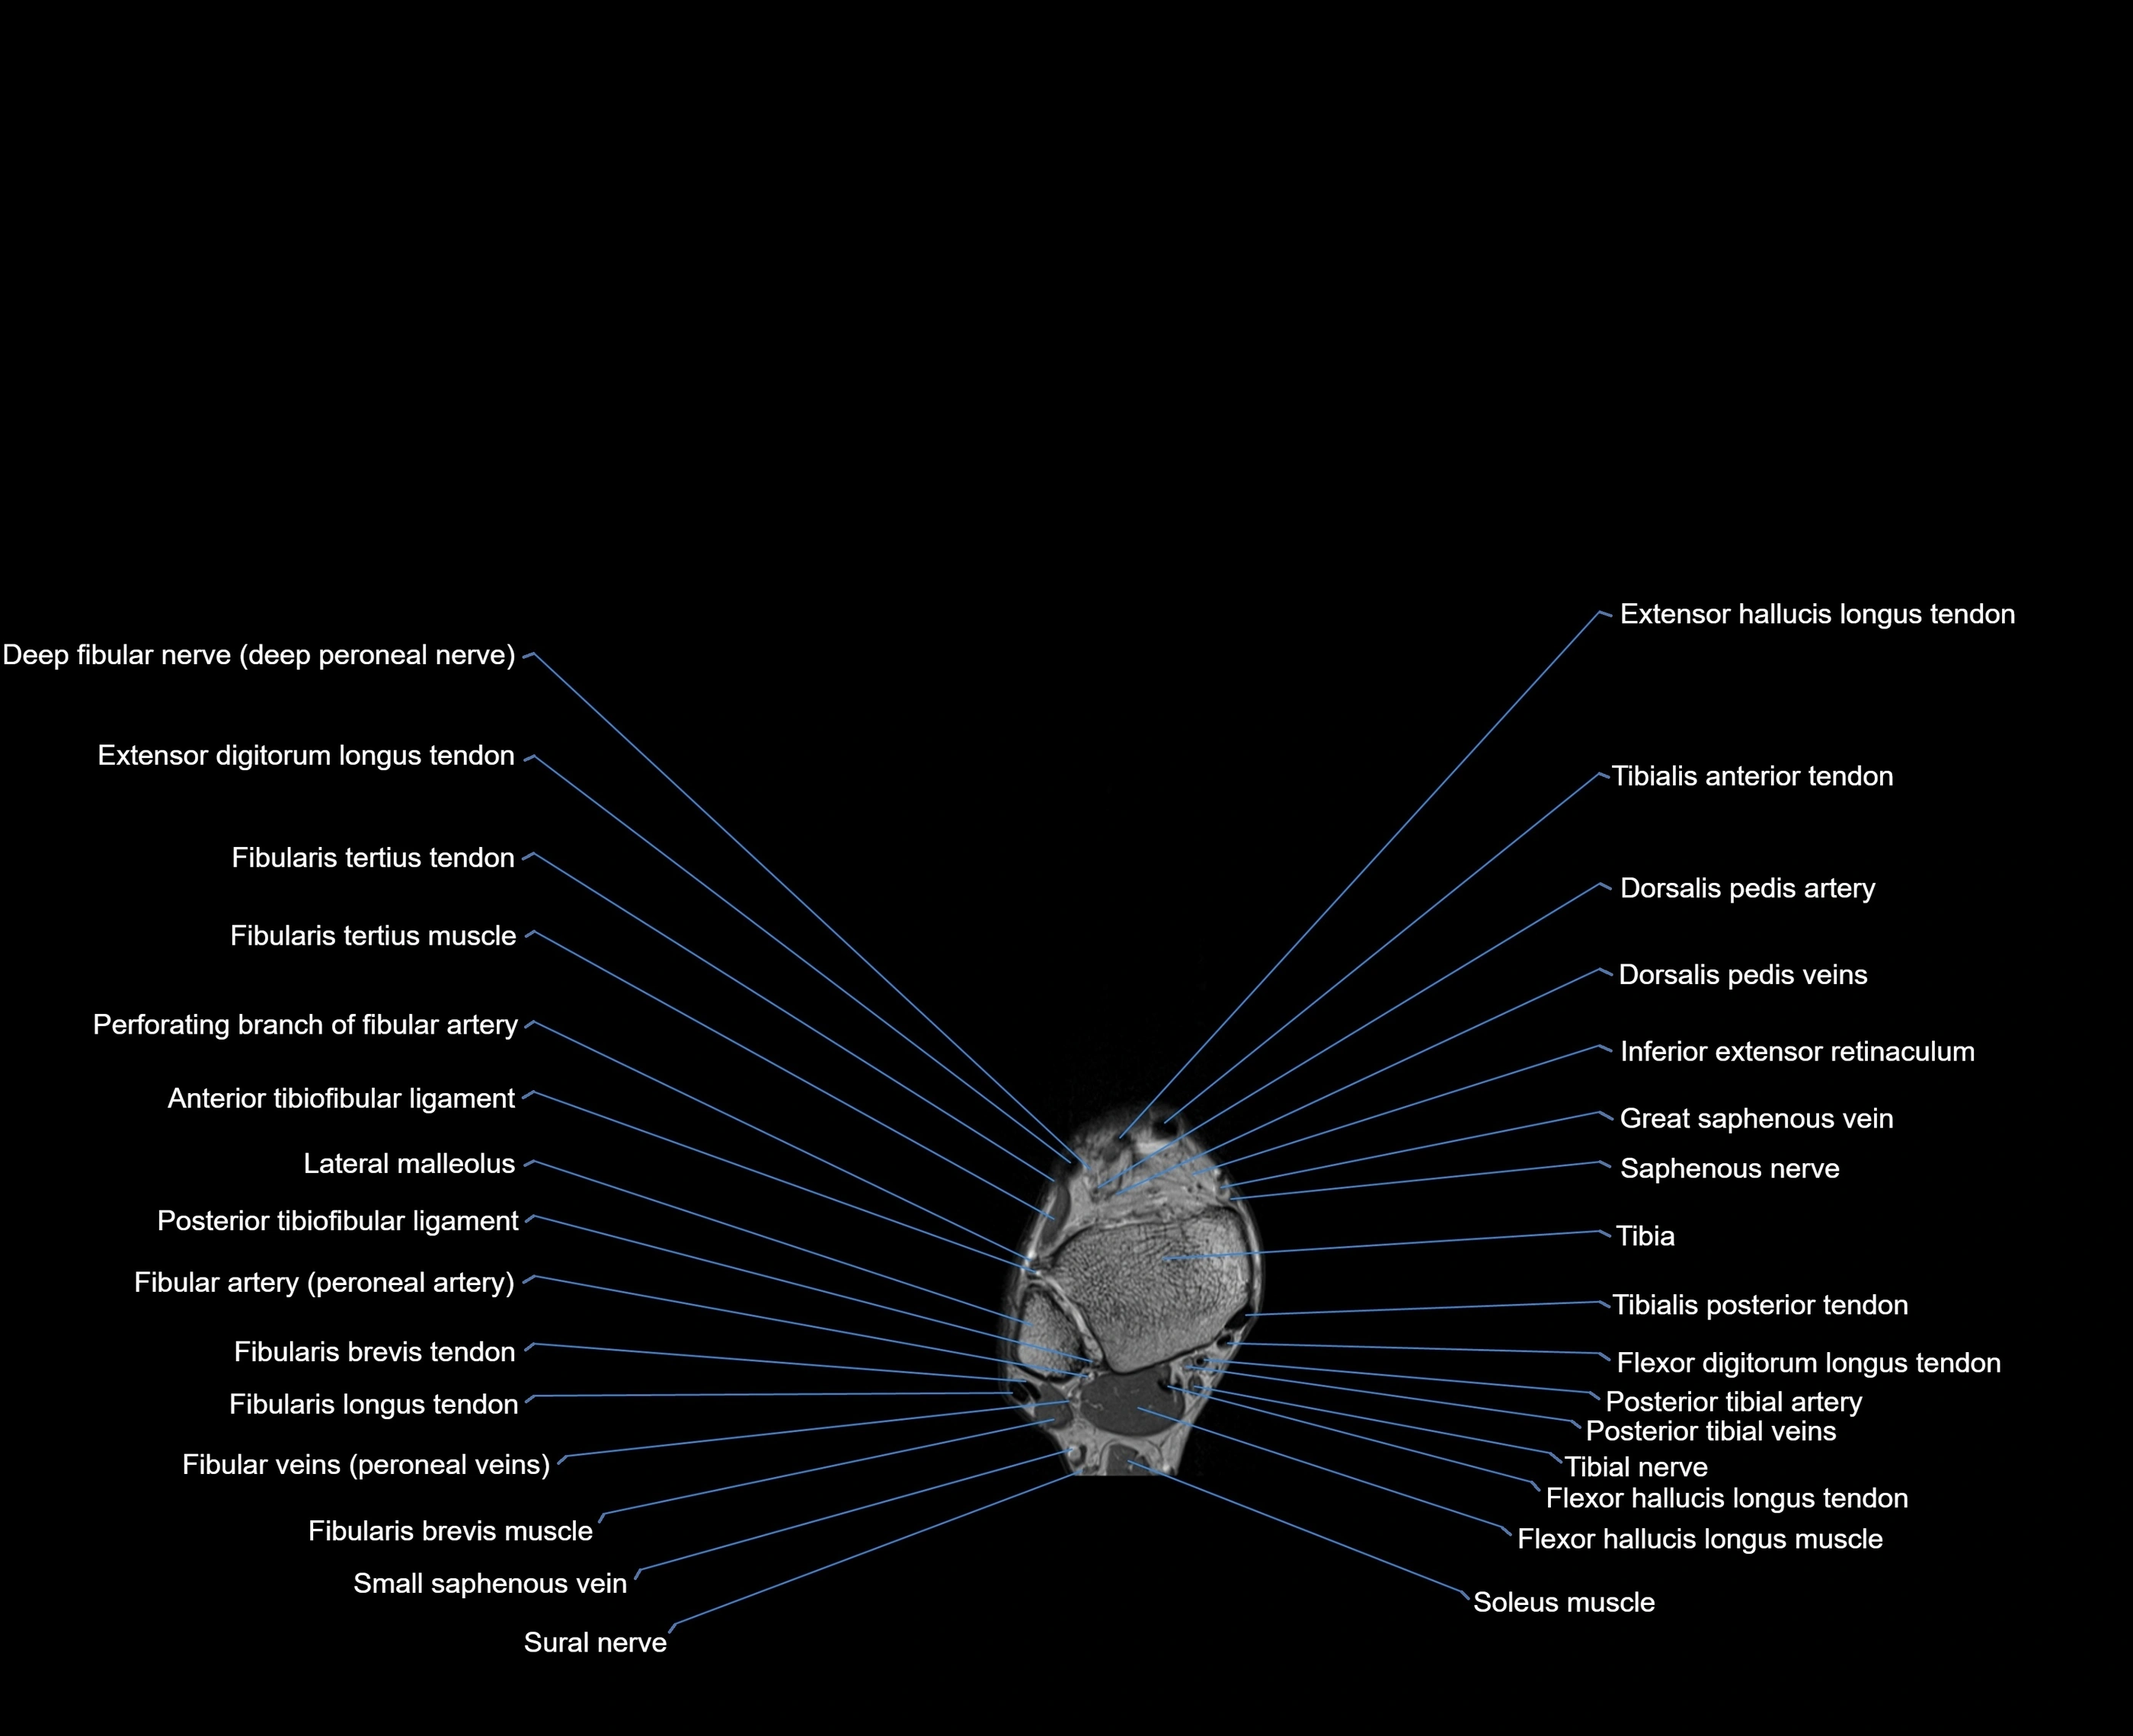

MRI image